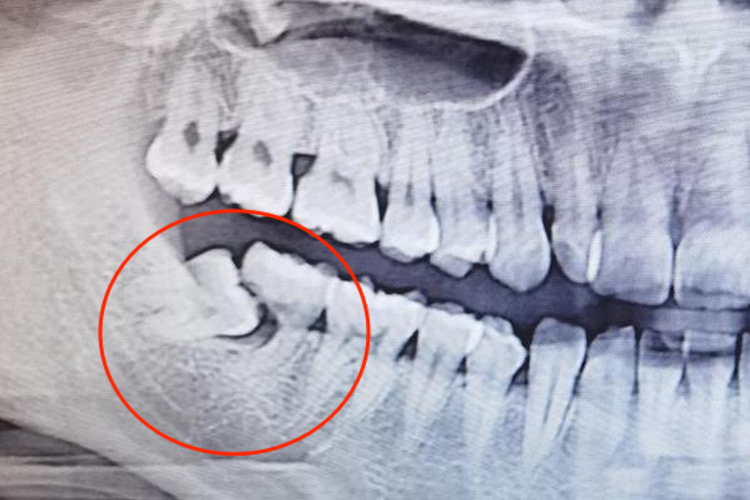

如大牙存在严重的根尖周病变,已不能用根管治疗、根尖手术或牙再植术等方法进行保留,也需要拔除。